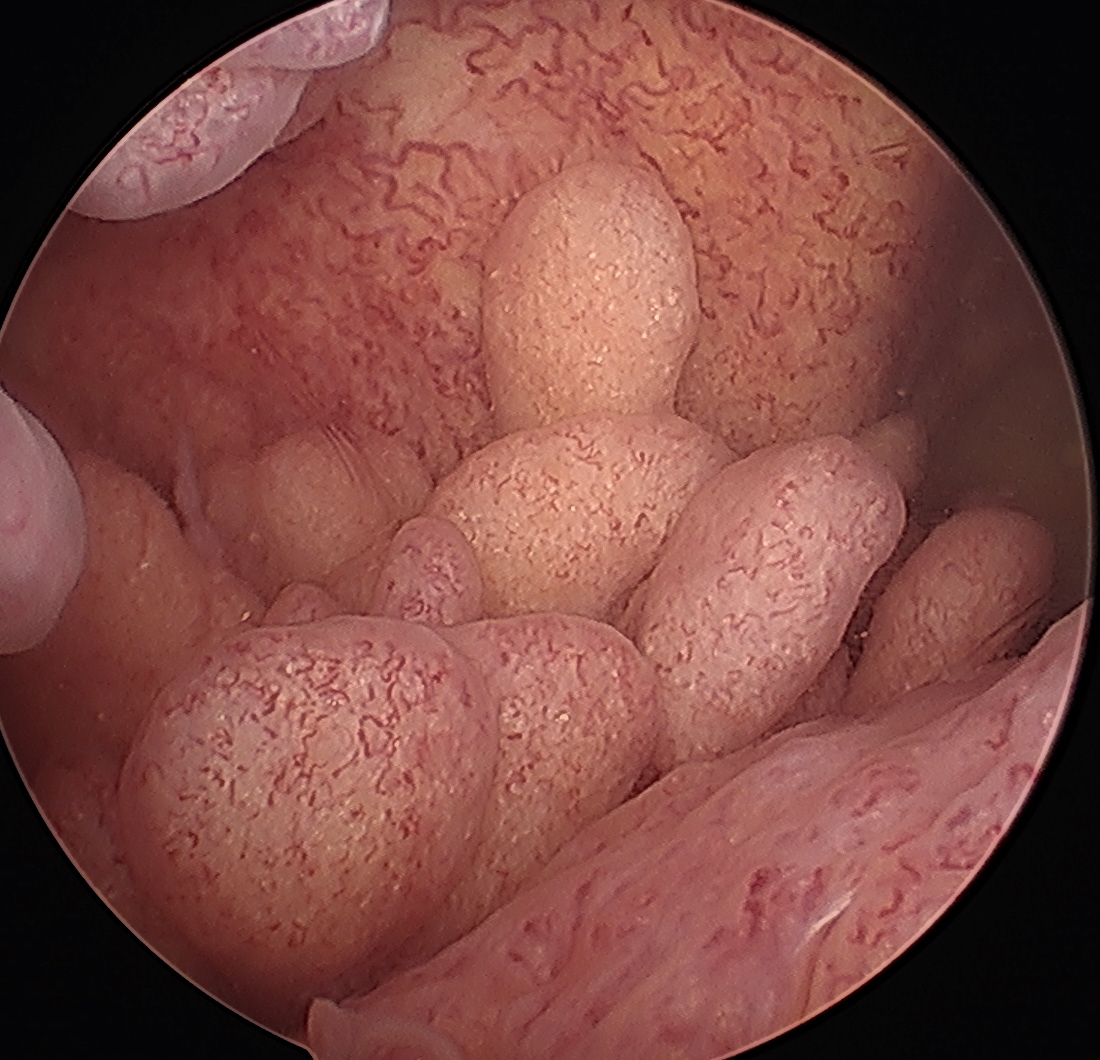

Arthroscopy

Yellow brown polypoid / frond like villous synovitis